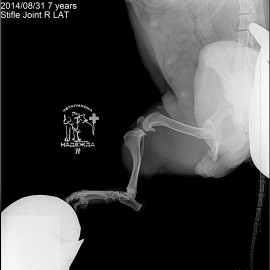

Наш пациент собака породы джек-рассел-терьер по кличке Эльза. Обратились с жалобами на остро развившуюся хромоту на правую заднюю конечность. После проведенных исследований был поставлен диагноз: разрыв передней крестообразной связки правого коленного сустава. Была проведена операция: TPLO.

Снимок 1 до операции.